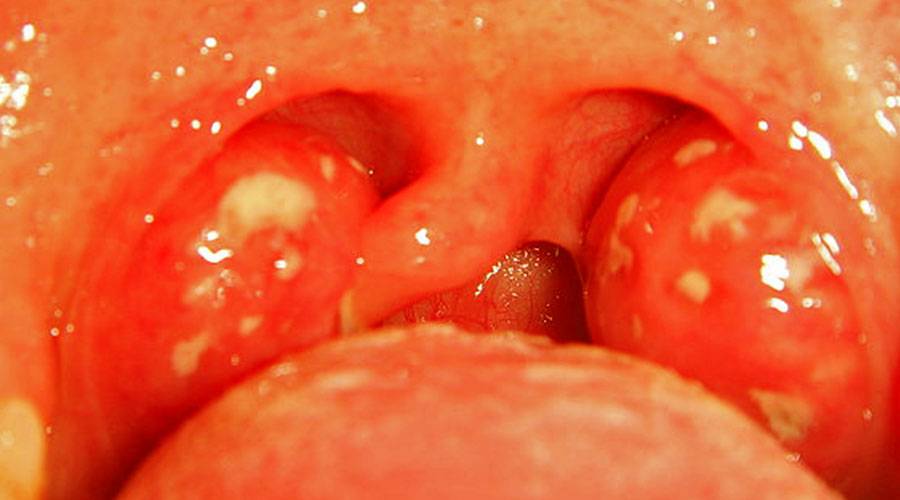

Фолликулярная ангина — характеризуется сильной болью в горле, усиливающейся при глотании, и иногда отдающая в уши. Температура тела может повышаться до 38-40 °С, симптомы интоксикации — головная боль, слабость, озноб, тянущая боль в пояснице. Увеличиваются подчелюстные лимфатические узлы, на нёбе и миндалинах видны маленькие бело-желтые точки.

Лакунарная ангина у взрослых — протекает тяжелее, чем фолликулярная. Общие симптомы ангины такие же, только значительно выраженные. Нёбо приобретает ярко-красный цвет, на миндалинах отмечается налёт жёлтого цвета. В редких случаях температура поднимается до 40° С.

Налет на миндалинах при ангине.

- Увеличиваются, отекают, краснеют небные миндалины. При бактериальной форме заболевания на них могут быть язвы, серозный или гнойный налет. При герпетической ангине гланды покрываются характерными пузырьками с серозным содержанием. При кандидозной ангине налет на гландах белый.

- На гландах образуются гнойные пробки.